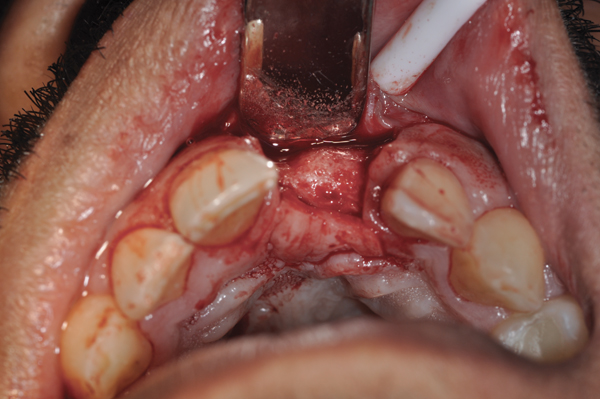

Fig 5. Bone graft placed in the socket.

Figure 5

Fig 6. d-PTFE barrier in position, and the flap sutured.

Figure 6